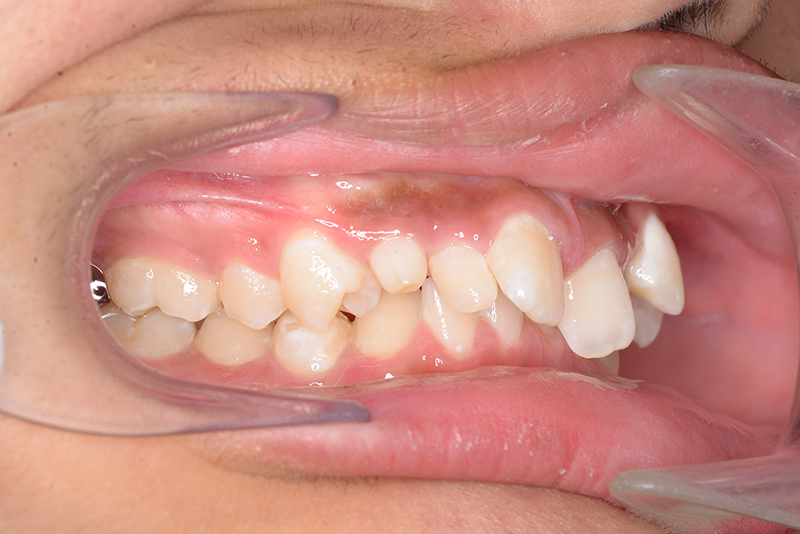

動的治療終了時

FP・IOP

批評・予后 側貌はconcave typeであり、下顎歯列は叢生が少ないこと、右上3欠損、左右上2は矮小歯であることを考慮して右上C、左側2抜歯とした。治療後はアンテリアレシオの調和を図るべく右上2は暫間的修復(CR)にて歯冠幅径を大きくしている。保定終了後には同部位は最終補綴を装着する予定である。